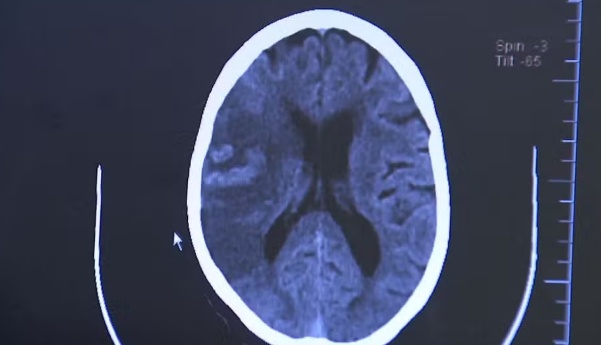

Diagnóstico e reabilitação

O diagnóstico é feito por tomografia computadorizada ou ressonância magnética do crânio. “Esses exames permitem detectar a área afetada e definir se é um AVC isquêmico ou hemorrágico”, diz Chaddad.